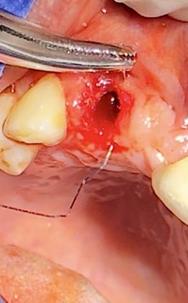

Sindesmotomía con un periostótomo de molt # 9, posteriormente se realizó la luxación con un elevador recto, buscando el punto de apoyo, seguido se efectuó la prensión con el fórceps 150 en el diente con sumo cuidado de no tocar la encía colocándolo hasta el cuello dental, haciendo movimientos de lateralidad y rotación hasta lograr la dilatación del alveolo, y finalmente la tracción del órgano dentario, observando que la raíz este integra, y que estructuras alrededor estén conservadas, de la misma forma se revisó el alveolo en busca de la presencia de granulomas o espículas óseas, una vez ya revisado se procedió al curetaje, con una cucharilla de lucas, se introdujo y se dio paso al retiro del exudado purulento, se realizó irrigación del alveolo con solución fisiológica, una vez limpio se realizó una sutura simple con sutura nylon, seda # 3/0 en el medio del alveolo con la finalidad de aproximar rebordes, evitar su contaminación por el ingreso de comida, además generar una mejor cicatrización en una zona estética , finalmente se aplicó presión por medio de una gasa que mordió el paciente por un lapso de 30 minutos, para contribuir con una hemostasia adecuada.

Figura 7. Exodoncia de la unidad dental, revisión del alveolo, curetaje y retiro de exudado purulento con cucharilla de lucas.

Elaboración: Los autores.